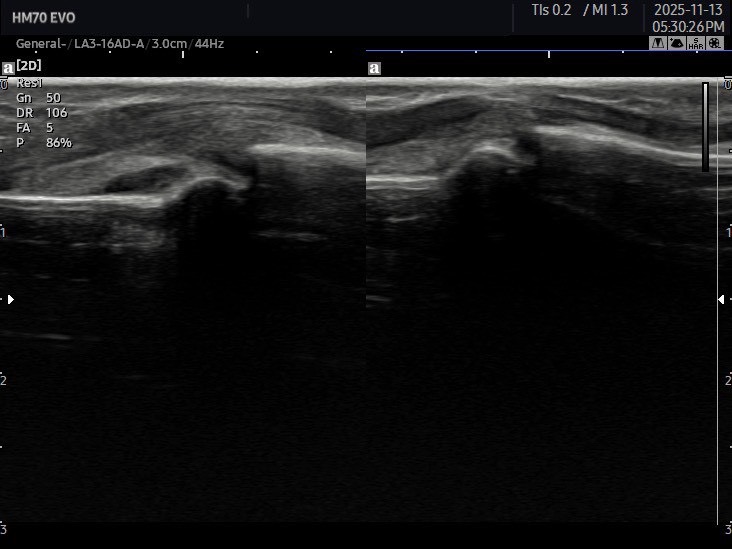

当院ができること

掌側板損傷は、見た目だけでは「軽い突き指」と区別がつきにくいため、

当院ではエコー(超音波画像観察装置)を使い、

損傷の有無・程度をしっかり確認しています。

-

靱帯の断裂がないか

-

付着部の剥離骨折がないか

-

関節のぐらつき(不安定性)があるか

これらを評価することで、治療方針がはっきりします。

「湿布貼って様子を見るだけ」で改善が遅れることが多いので

まずは正しい鑑別が大切です。